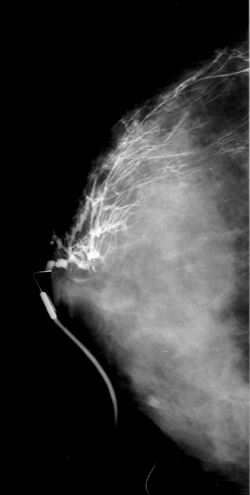

Als screening, om eventueel een gezwel

tijdig te

ontdekken |

Bij klinisch vermoeden van een mogelijk

gezwel (vb. een

knobbel dat voelbaar is). |

Opvolgen van gekende borsttumoren |

Bij zwangerschap en borstvoeding |

Bij heel jonge vrouwen, daar er dan veel

klierweefsel is

en de mammografie onvoldoende informatie zal geven |